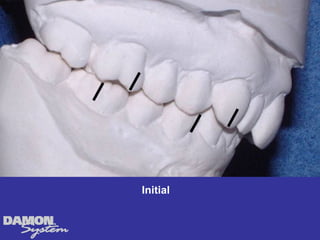

Archwire adapted toinitial and final arch form

Initial to finalarch length increased 13 mm Arch width accounts for space gained